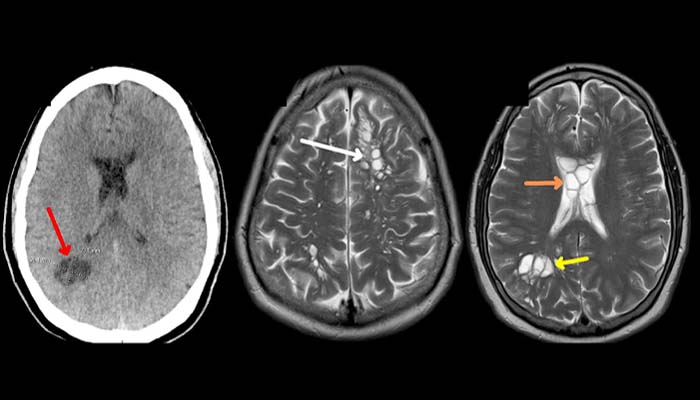

Later, after a scan, it was found that there are tapeworm larval cysts in his brain that become the reason for ‘cysticercosis’.

As per US Centers for Disease Control and Prevention, cysticercosis is an infection of parasitic tissues that occurs when someone swallows tapeworm eggs passed through the feces of someone with intestinal tapeworm.

Then these tapeworm eggs become larval cysts that may infect the muscle, tissues or brain, CNN reported.